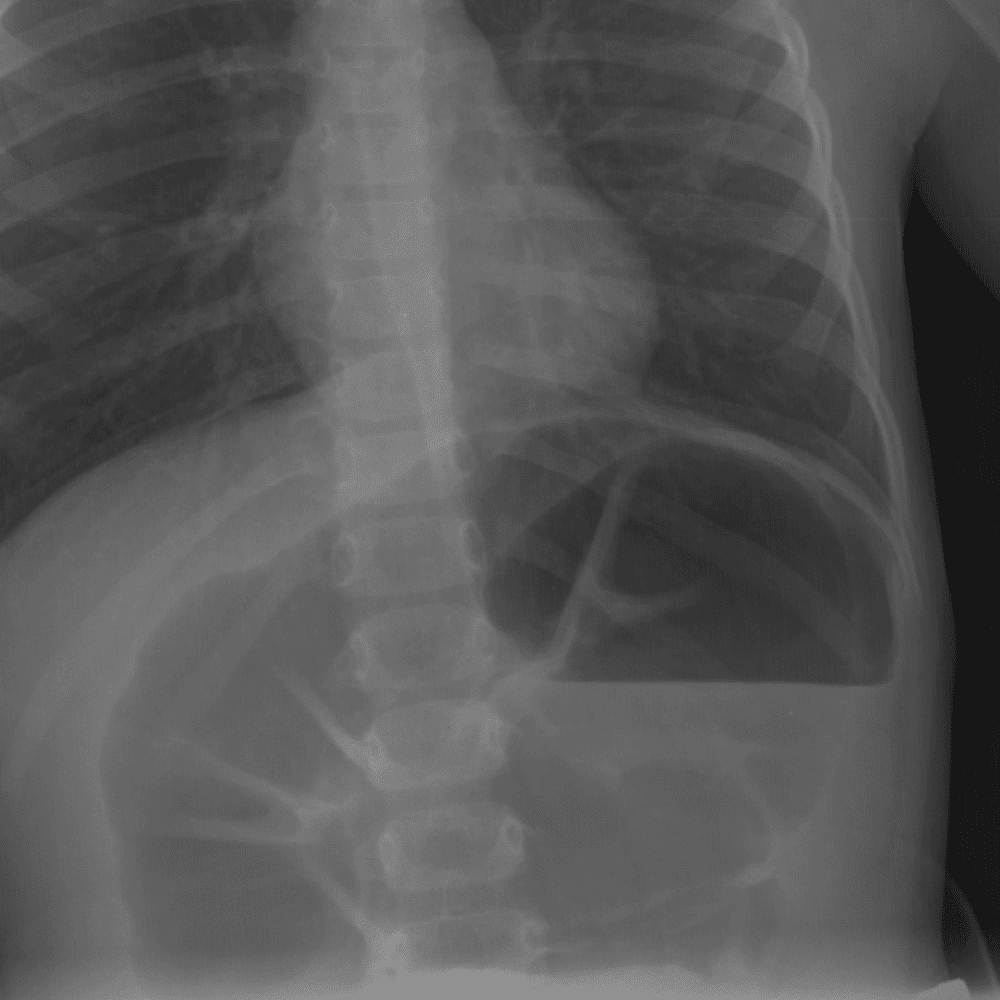

Peds Abdomen

Practice

Simulates call by including subtle or difficult cases and some normals.

30 cases